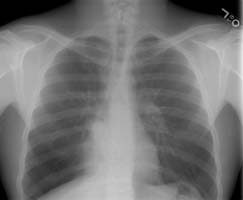

The chest radiograph revealed a right infrahilar density and increased retrocardiac density on the right (yellow arrows). The was hyperlucency laterally within the right lower lobe and the findings were felt to be suspicious for right lower lobe volume loss. The lateral exam is also provided by was unrevealing.

(Click on small images to view larger radiographs)